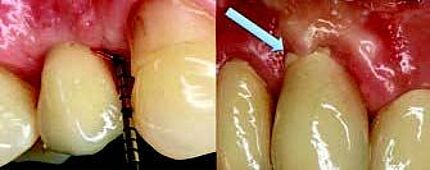

Ein eindrücklicher Case Report ist in der Quintessenz Zahnmedizin publiziert: Der Erhalt der ursprünglichen Gewebearchitektur in der ästhetischen Zone ist eine zentrale Herausforderung in der modernen, zahnärztlichen Implantologie. Wenn die Voraussetzungen für eine Sofortimplantation mit einer prothetischen Sofortversorgung gegeben sind, ist dies ein möglicher Weg die ursprüngliche Morphologie der Hart- und Weichgewebe weitgehend zu erhalten. Der vorliegende Beitrag definiert die Begriffe Sofortimplantation, Sofortversorgung sowie Sofortbelastung und illustriert einen klinischen Fall bei dem nach Fraktur eines Frontzahnes eine Sofortimplantation mit provisorischen Sofortversorgung realisiert werden konnte.

Zeitschrift: Quintessenz Zahnmedizin

Ausgabe: 11/2022, S. 1028 - 1036

Autoren: Dr. Christopher Prechtl, PD Dr. Daniel Hellmann, Dr. Dr. Hans Ulrich Brauer, M.A., M.Sc.